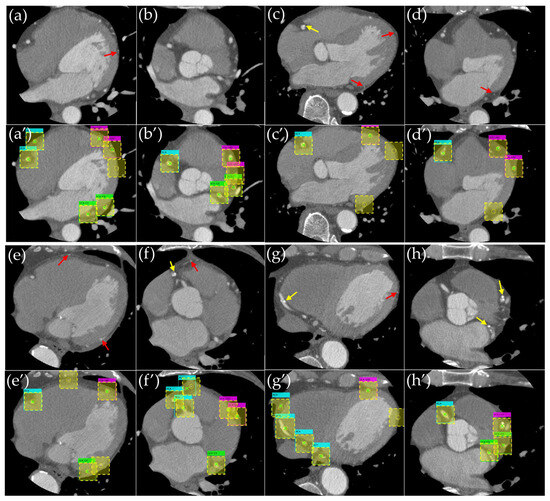

- We propose an annotation method that defines bounding boxes for major coronary arteries (RCA, LCA-LAD, and LCA-CX) in cross-sectional CCTA slices, enabling systematic and reproducible labeling.

- We develop and evaluate a deep learning pipeline using object detection techniques, integrating conventional metrics (e.g., Average Precision) with novel criteria (e.g., localization error) to capture the distinct ways detection failures manifest.

3.1. Evaluation of the Object Detection Model

3.2. Evaluation of Detection Accuracy Using Additional Metrics